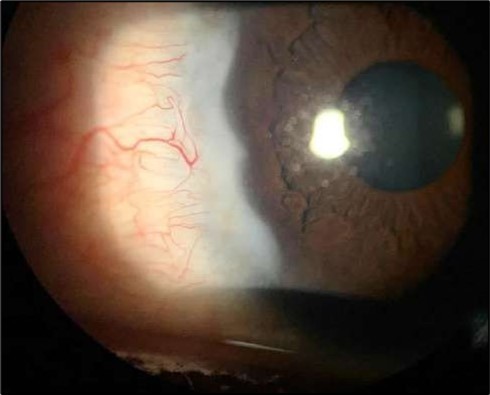

At six-months follow-up post-resection, the ulcer showed progressive epithelialization with no recurrence. Oral prednisolone was gradually tapered and stopped. The patient remains under regular ophthalmology follow-up with stable ocular findings Figure 6.

Figure 6.Six-month follow-up image showing a stable ocular surface, and absence of ulcer recurrence. The cornea appears clear centrally, with stromal scarring limited to the periphery.

Serial anterior segment OCT was employed throughout treatment to monitor corneal changes and response to interventions. Figure 7a, Figure 7b, Figure 7c, Figure 7d illustrate the ulcer’s progression: initial severity, minimal early response to medical therapy, post-operative healing after conjunctival resection, and sustained recovery at six-month follow-up.

Figure 7d.(6 months follow-up): OCT demonstrates complete structural restoration of the cornea with a smooth anterior contour, full re-epithelialization, and resolution of the ulcer defect. Mild residual stromal hyperreflectivity remains, consistent with fibrotic scarring. There is no evidence of epithelial breakdown or recurrence, indicative of a quiescent disease state